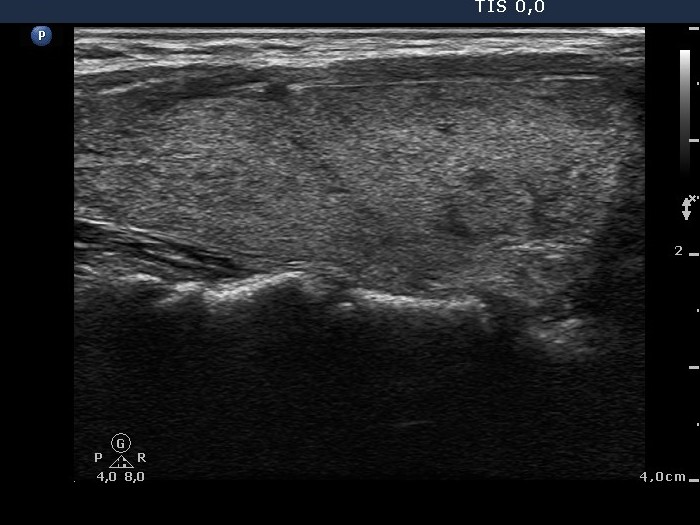

Follow-up investigation 36 months after first visit (ultrasonographic picture 2)

Patient on daily 10 mg methimazole therapy in euthyroid state

Right lobe, longitudinal scan.